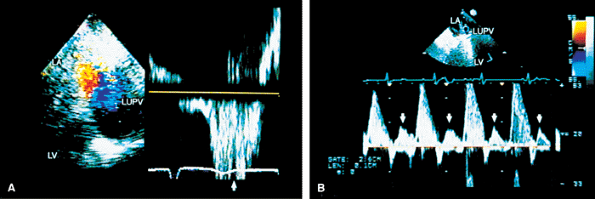

FIGURE 5.21. Porcine mitral prosthesis: paravalvular regurgitation. A. A laterally located area of prosthetic (MP) dehiscence (arrow). B–D. An eccentric jet of mitral regurgitation (MR) (arrowheads) originating in the area of prosthetic (P) dehiscence. E. Color M-mode demonstrates systolic backflow (arrows) in the left upper pulmonary vein (LUPV), indicative of severe MR. After repair, the dehisced area is no longer seen (F), and there is absence of systolic backflow in LUPV (G). AS, atrial septum; FA, flow acceleration; LA, left atrium; LV, left ventricle; RA, right atrium; RV, right ventricle. |

FIGURE 5.23. Mitral prosthesis: valvular regurgitation. A–C. S represents the valve stents, and the arrow in B points to a suture. Color Doppler examination demonstrates three jets of mitral regurgitation (MR) (E) associated with two areas (arrows) of prominent flow acceleration on the ventricular side of the prosthesis in D. F. Systolic backflow in left atrial appendage (LAA) indicates severe MR. Although MR was pansystolic in this patient, the systolic backflow occurred only in mid- and late systole, because it takes some time for the MR jet to travel to LAA from the prosthesis. G. Postoperative study shows absence of severe MR and two jets (arrows) of mild, normal mitral prosthetic (MP) regurgitation. LA, left atrium; LUPV, left upper pulmonary vein; LV, left ventricle. |